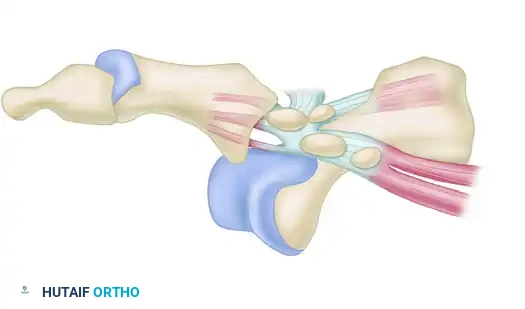

In a Type I dislocation, the intersesamoid ligament remains intact. The entire plantar plate and sesamoid complex are avulsed from their metatarsal attachment and displace dorsally over the metatarsal head.

FIGURE 88-78 B: Type I dislocation. The intact intersesamoid ligament traps the metatarsal head, making closed reduction impossible.

Surgical Warning: Type I dislocations are almost universally irreducible by closed means. The metatarsal head becomes tightly incarcerated between the FHB tendons, the intact intersesamoid ligament, and the plantar plate. Applying longitudinal traction without hyperextension will only tighten this "noose" around the metatarsal neck.

In a Type IIA dislocation, the intersesamoid ligament is ruptured. The medial and lateral sesamoids separate, allowing the metatarsal head to pass between them.

FIGURE 88-78 C: Type IIA dislocation. The ruptured intersesamoid ligament typically allows for successful closed reduction.